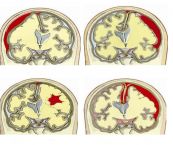

Máu tụ dưới màng cứng hình thành giữa màng cứng và màng nhện. Máu tụ ngoài màng cứng là khối máu tụ hình thành ở khoang ảo giữa màng cứng và xương sọ. Để hiểu rõ hơn về hội chứng này, mời các bạn cùng tham khảo bài viết sau đây!

Não có thể bị tổn thương do hộp sọ bị nứt hoặc đâm xuyên, ví dụ như trong trường hợp tai nạn xe cộ, rơi ngã hoặc trúng đạn, một diễn tiến bệnh tật. Để biết rõ hơn về hội chứng này, mời các bạn cùng eLip tìm hiểu trong bài viết dưới đây!

Chấn thương sọ não hở bao gồm tất cả các chấn thương sọ não gây rách màng cứng, khai thông não bộ với bên ngoài, loại này gây nguy cơ nhiễm khuẩn não cao. Để biết thêm về hội chứng nguy hiểm này, mời các bạn tham khảo bài viết dưới đây!